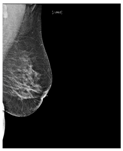

| ACR Class | Feature | Tissues Proportion | Example |

|---|---|---|---|

| A | Fatty | Less than 25% dense tissue | ![]() |